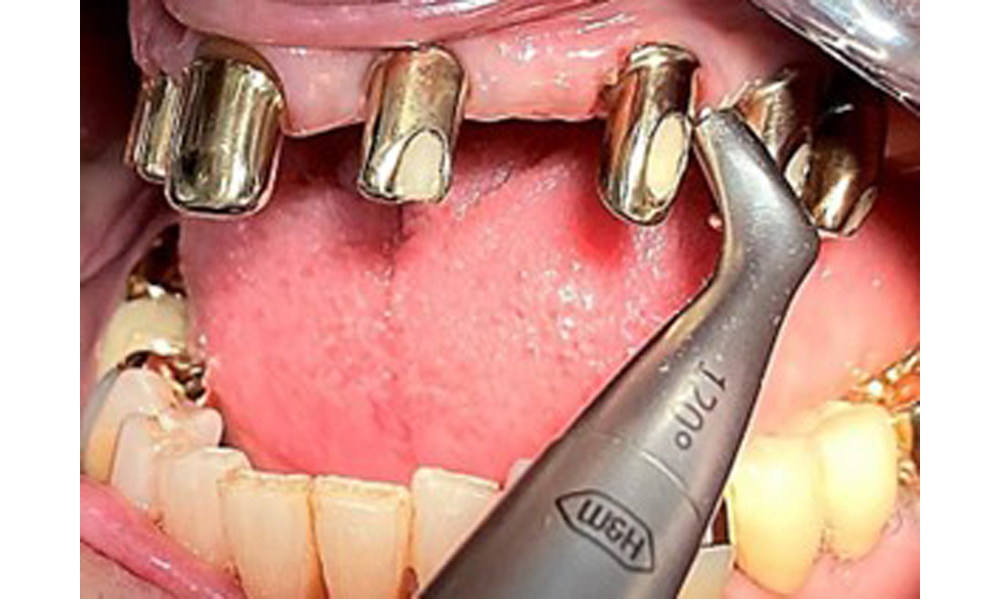

Processing the implant surface with manual titanium instruments.

Fig. 10: Processing the implant surface with manual titanium instruments.

Illustration of a PEEK ultrasonic tip (Proxeo Ultra, W&H, shown here) for processing implant surfaces with mineralized plaque (no mineralized plaque was observed in the present case, this is a schematic illustration).

Fig. 11: Illustration of a PEEK ultrasonic tip (Proxeo Ultra, W&H, shown here) for processing implant surfaces with mineralized plaque (no mineralized plaque was observed in the present case, this is a schematic illustration).

Sonic/ultrasonic, or conventional manual instruments may be used to remove calculus and concretions present on the natural teeth (8). Titanium or plastic curettes (Fig. 10), or a plastic or PEEK attachment (Fig. 11) during ultrasonic treatment, should be used to remove mineralized plaque from implants to avoid damaging the implant surfaces.